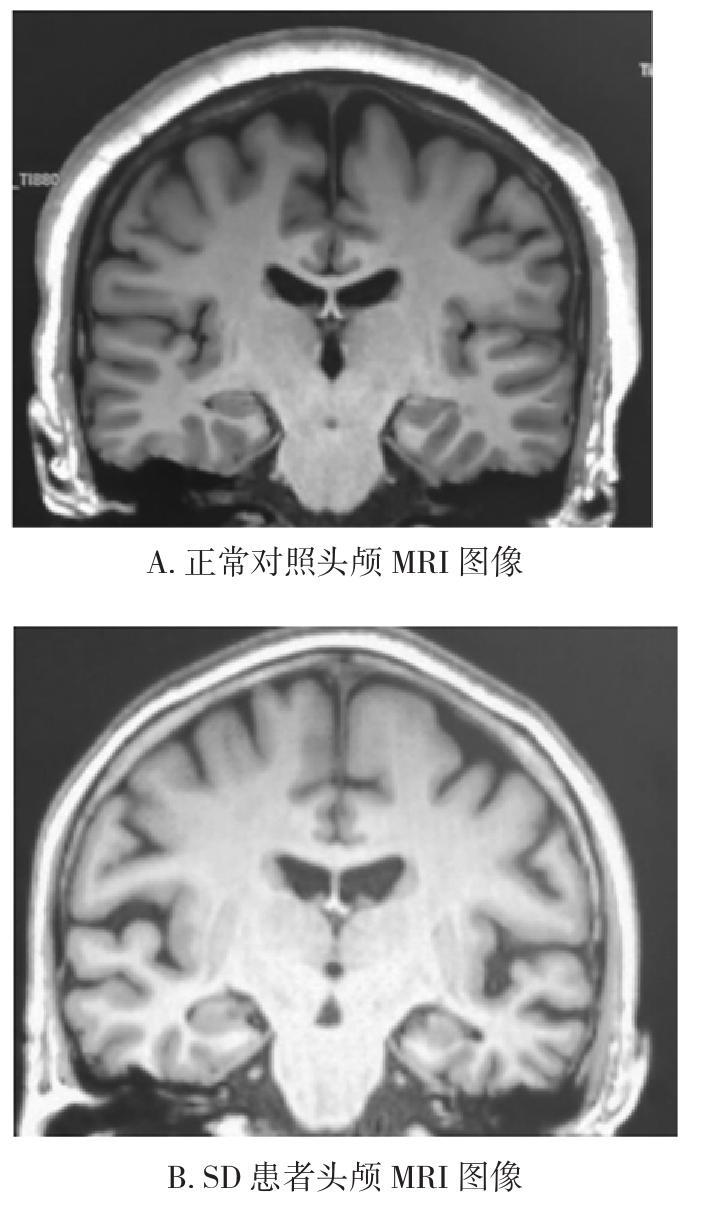

• 剑桥语义测验在语义性痴呆患者中的应用研究

2021, 46(11):1291-1295. DOI: 10.13406/j.cnki.cyxb.002908

摘要 (111) HTML (444) PDF 2.21 M (224) 评论 (0) 收藏

摘要:目的: 检测剑桥语义测验(Cambridge semantic memory test battery,CST)在语义性痴呆(semantic dementia,SD)患者中的研究应用。 方法: 对26例SD患者、25例正常对照组受试者均进行语言量表及其他包括简易精神状态检查量表(mini-mental state examination,MMSE)和蒙特利尔认知评估(Montreal cognitive assessment,MoCA)在内的全面的神经心理学测评。 结果: ①SD组整体测评结果均差于正常对照组(P<0.001);②CST的4个分项测验在检测SD患者与正常对照组时的AUC值分别为0.984(95%CI=0.951~1.000)、0.915(95%CI=0.826~1.000)、0.898(95%CI=0.808~0.988)、0.857(95%CI=0.733~0.980)(P<0.001)。③采用双变量分析CST结果与MMSE、MoCA及综合性认知评估、日常生活能力量表(activity of daily living scale,ADL)、临床痴呆评定量表(clinical dementia rating scale,CDR)等结果在0.01层面具有显著相关性(P<0.001);④SD组患者核磁显示SD患者具有明显的颞叶前下部萎缩,且侧重于左侧,并与相关神经心理学量表测评结果相符。 结论: CST可用于筛查SD患者。